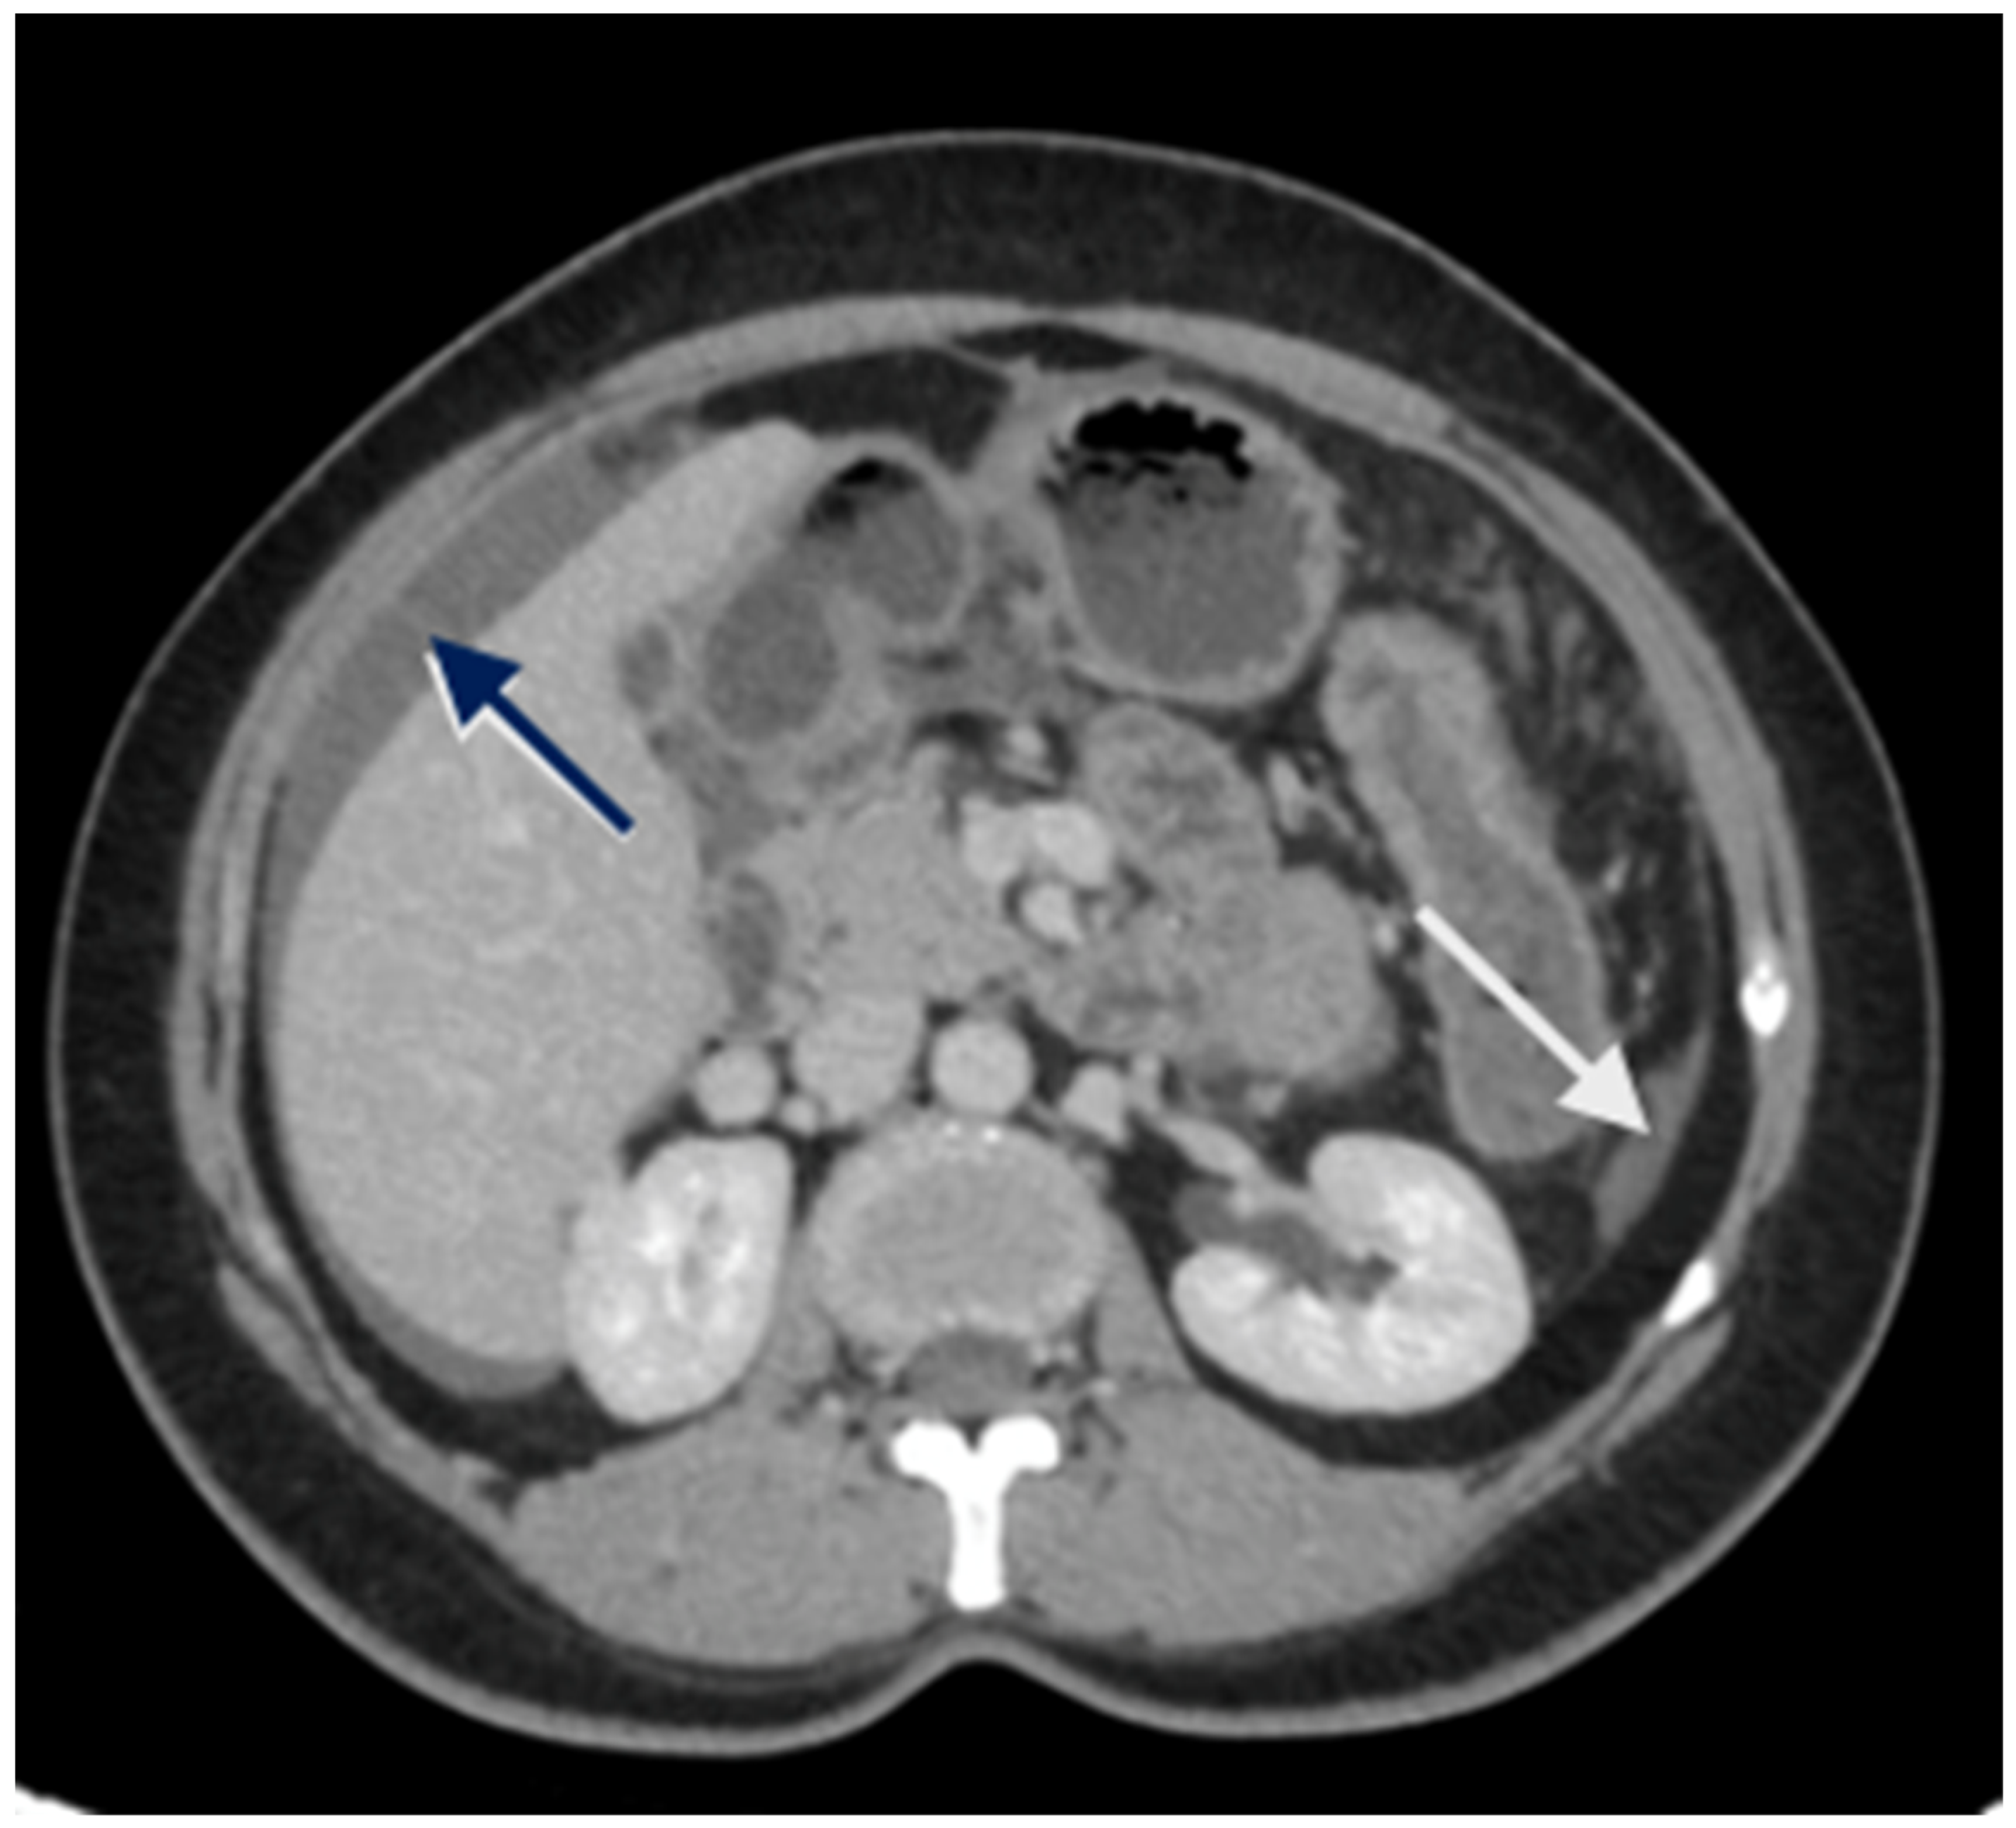

Imaging has two significant roles: the first is the detection of limited disease and all sites of disease in the upper abdomen, and the second is predicting resectability. The most common study is a contrast-enhanced CT scan of the thorax, abdomen, and pelvis [47]. Several investigators have shown that a CT scan underestimates the extent of peritoneal disease [48,49,50]. The spread of peritoneal disease is usually reported using the peritoneal cancer index (PCI). The accuracy in predicting the extent of upper-abdominal disease is not studied separately; the overall accuracy ranges from 15 to 80% [48,49,50]. Peritoneal disease can present as a thickening and/or enhancement of the parietal peritoneum (the subphrenic peritoneum) or discrete nodular deposits (Figure 1).

Figure 1.

Peritoneal thickening and enhancement (white arrows) as seen on a contrast-enhanced CT scan suggestive of the presence of disease.

Loculated fluid collections adjacent to the liver, indentation of the liver surface, and fluid in the sub-hepatic region are some pre-emptive signs of underlying peritoneal disease (Figure 2). A contrast-enhanced MRI of the abdomen and pelvis with a dedicated protocol for the detection of peritoneal disease is being used at several centers and has shown to be more accurate in predicting the disease extent [51,52].

Figure 2.

CT scan showing nodular peritoneal deposit on the subphrenic peritoneum (white arrow); loculated fluid collection (blue arrow).